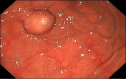

Rare Subepithelial Mass Diagnosed as Gastric Splenosis via EUS-FNA